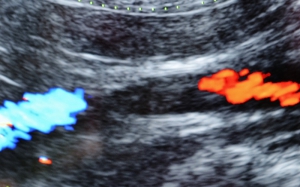

腹部の超音波検査では大動脈の中に血栓が確認できることもあります。左下が血栓を中心に観察した血流のドップラーエコーによって左右の着色部位には、青→赤の血液の流れがあること、その間の黒い部分は血栓によってその流れが遮断されていることを示しています。右下に見やすいように血管の模式図を重ねてありますが、黄色矢印に囲まれた部分が血栓を示しています。(左が頭です。)